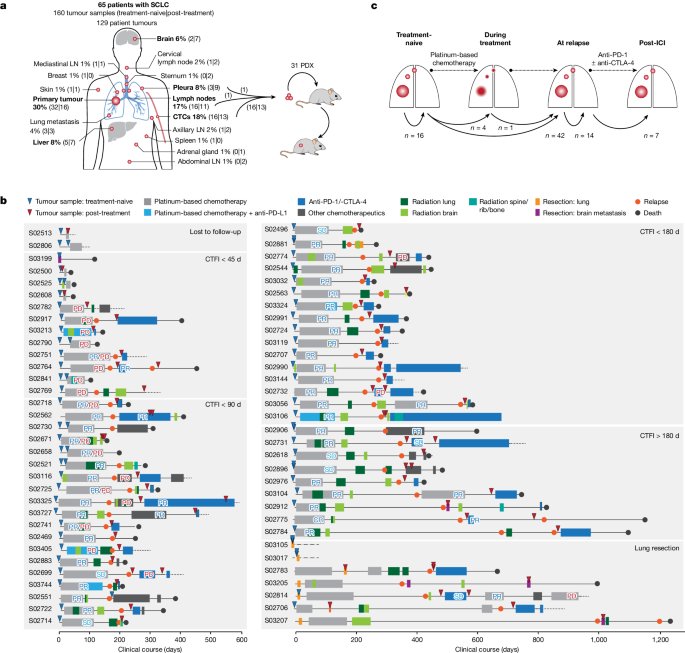

Tumour specimens and clinical data

We collected 160 tumour specimens from 65 patients with SCLC under institutional review board approval and performed whole-exome, genome and transcriptome sequencing of samples with an average tumour purity of 85% (Fig. 1a–c and Supplementary Tables 1 – 3 ). We most frequently sampled the primary lung tumour, pulmonary lymph nodes, liver, pleura and brain metastases. Furthermore, patient-derived xenotransplants were established from fine-needle biopsies or circulating tumour cells (CTCs), which have been previously shown to recapitulate the genomic profiles of patients’ tumours 12 , 13 (Fig. 1a and Methods ). The histology of SCLC was confirmed in all cases; additional components of adenocarcinoma or large-cell neuroendocrine carcinoma (LCNEC) were identified in three patients (Supplementary Table 1 ). The clinical history was typical of SCLC and the majority of patients had received first-line treatment with platinum-based chemotherapy, achieving a median relapse-free interval of 88 days (Fig. 1b , Extended Data Table 1 and Supplementary Table 1 ). In line with clinical guidelines 14 we grouped patients according to their duration of response to first-line chemotherapy, referring to the chemotherapy-free interval (CTFI) of 45, 90 and 180 days (Fig. 1b ). At relapse, 80% of these patients ( n = 44 of 55) received additional lines of therapy, which included other chemotherapeutics or treatment with anti-PD-1 and/or anti-CTLA-4 ICIs (Supplementary Table 1 ).

a , Tumour sites sampled from 65 patients with SCLC. Frequently sampled sites are highlighted in bold. Tumours were acquired either at the time of first diagnosis (treatment-naive) or following initiation of treatment (post-treatment). Tumour samples analysed as patient-derived xenotransplant (PDX) models are indicated. b , Schematic overview of the clinical course of 65 patients with SCLC. Patients were ordered according to their duration of response to first-line platinum-based chemotherapy, referring to a CTFI of 45, 90 and 180 days (National Comprehensive Cancer Network (NCCN) guidelines). Patients who, following initiation of first-line treatment, were either lost to follow-up or underwent surgical resection of the primary tumour were sorted to separate panels. The treatment administered to each patient is annotated and the clinical response is described as either complete response (CR), partial response (PR), stable disease (SD), progressive disease (PD) or mixed response (PR/PD). A detailed description of all clinical characteristics is provided in Supplementary Table 1 and Methods . c , Schematic overview showing the analysis of paired, patient-matched tumour sites: paired studies of spatially distinct tumours at the time of first diagnosis (treatment-naive, n = 16); paired studies of tumour sites pretreatment and during treatment ( n = 5) or at clinical relapse following completion of first-line platinum-based chemotherapy ( n = 42); paired analyses of spatially distinct tumour sites at relapse ( n = 14); and analyses of tumours acquired before and after subsequent lines of treatment with ICIs ( n = 7). The scheme shows tumour sites in the lung, referring to primary and metastatic sites (larger and smaller red circles, respectively). LN, lymph node.

We analysed at least two tumour samples per patient, obtained at either single or multiple time points throughout the course of treatment. For interpatient comparisons we focused on paired studies of tumours acquired under distinct scenarios throughout the clinical course of the patients: (1) spatially distinct tumour samples in the treatment-naive setting at the time of first diagnosis ( n = 16); (2) temporally distinct tumours acquired at first diagnosis before initiation of therapy and either during first-line platinum-based chemotherapy ( n = 5) or following completion of chemotherapy ( n = 42); (3) spatially, but not temporally, separate tumours analysed solely at the time of relapse ( n = 14); and (4) tumours obtained before and after subsequent lines of treatment with immunotherapy ( n = 7) (Fig. 1c , Extended Data Table 1 and Methods ).